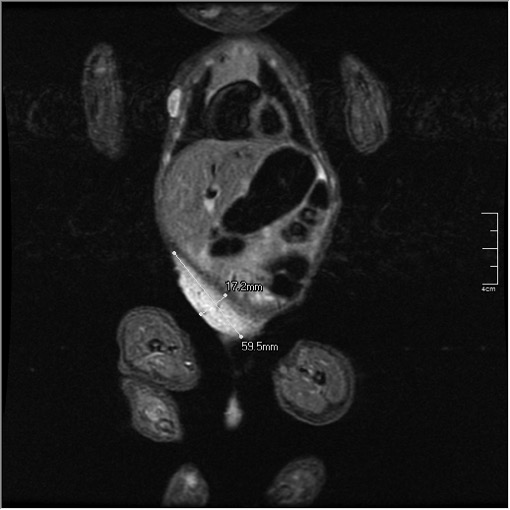

A one day old Moroccan boy was admitted to our neonatal unit with a giant tuberous right abdominal haemangioma. The clinical examination revealed no other vascular tumours. There was no evidence of heart failure. Ultrasound and MRA documented a giant vascular structure suggestive of haemangioma. The tumor responded well to propranolol treatment.